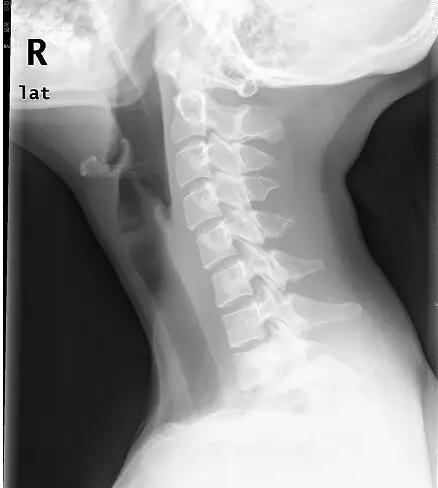

近日门诊接诊了一位18岁的花季少女小美,说是颈部疼痛难忍,已经半个月了,实在疼的不行了才来医院看看。拍片后显示:颈椎退变,生理弧度消失、变直。下面这张就是小张的颈椎侧位片。片子上,颈椎排列略呈“S”形。而不象是正常的“C”形。

而像小美这样造成颈椎生理弧度消失、变直的原因主要是平常经常低头看书写字,卧床看电视、玩手机,喜欢睡高枕等不良习惯。